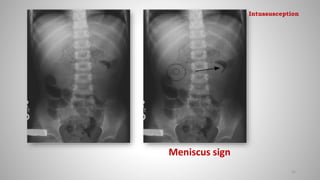

Imaging features:

Plain X-ray(Abd)

• Plain radiograph is normal in 25%.

• Small tissue mass and crescent of air around the intussuceptum in the

right abdomen.

• Small bowel obstruction

• Paucity of bowel gas distally

• Meniscus sign: Crescent of gas within colonic lumen that outlines the

apex of intussusceptum

Meniscus sign